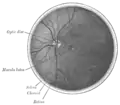

The interior of the posterior half of the left eyeball